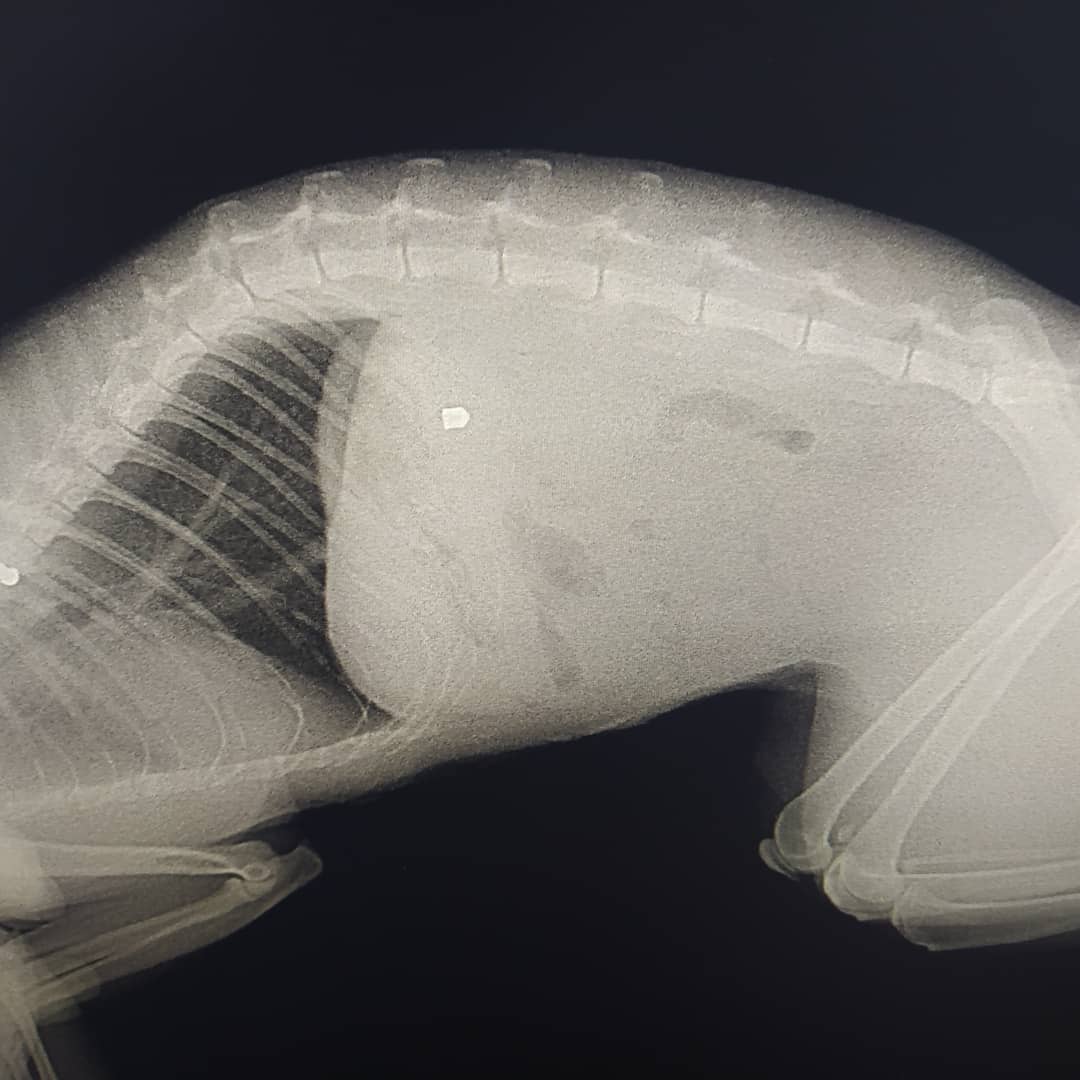

Об этом в Instagram сообщает местная жительница, ее коту прострелили селезенку.

"Вчера кот вечером пришел с раной на животе. Мы повезли его в клинику. Там сказали, что это выстрел с воздушки и что мы не первые, кто к ним обращается с такой проблемой с нашего района", - говорится в сообщении.

Это уже восьмой подобный случай в районе. Коту оказали помощь, затем провели операцию в другой больнице. Воздушка оказалось необычной, шансов было всего 20%. К счастью, все прошло успешно, но коту понадобится много времени на восстановление.